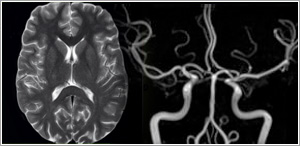

Neuro Imaging

MRI is considered the imaging modality of choice for most diseases affecting the central nervous system (brain and spine). Besides routine brain imaging, MRI is excellent at demonstrating diseases involving the internal auditory canals, pituitary gland, and orbits. Diffusion MRI is currently the earliest imaging modality for detecting acute stroke.